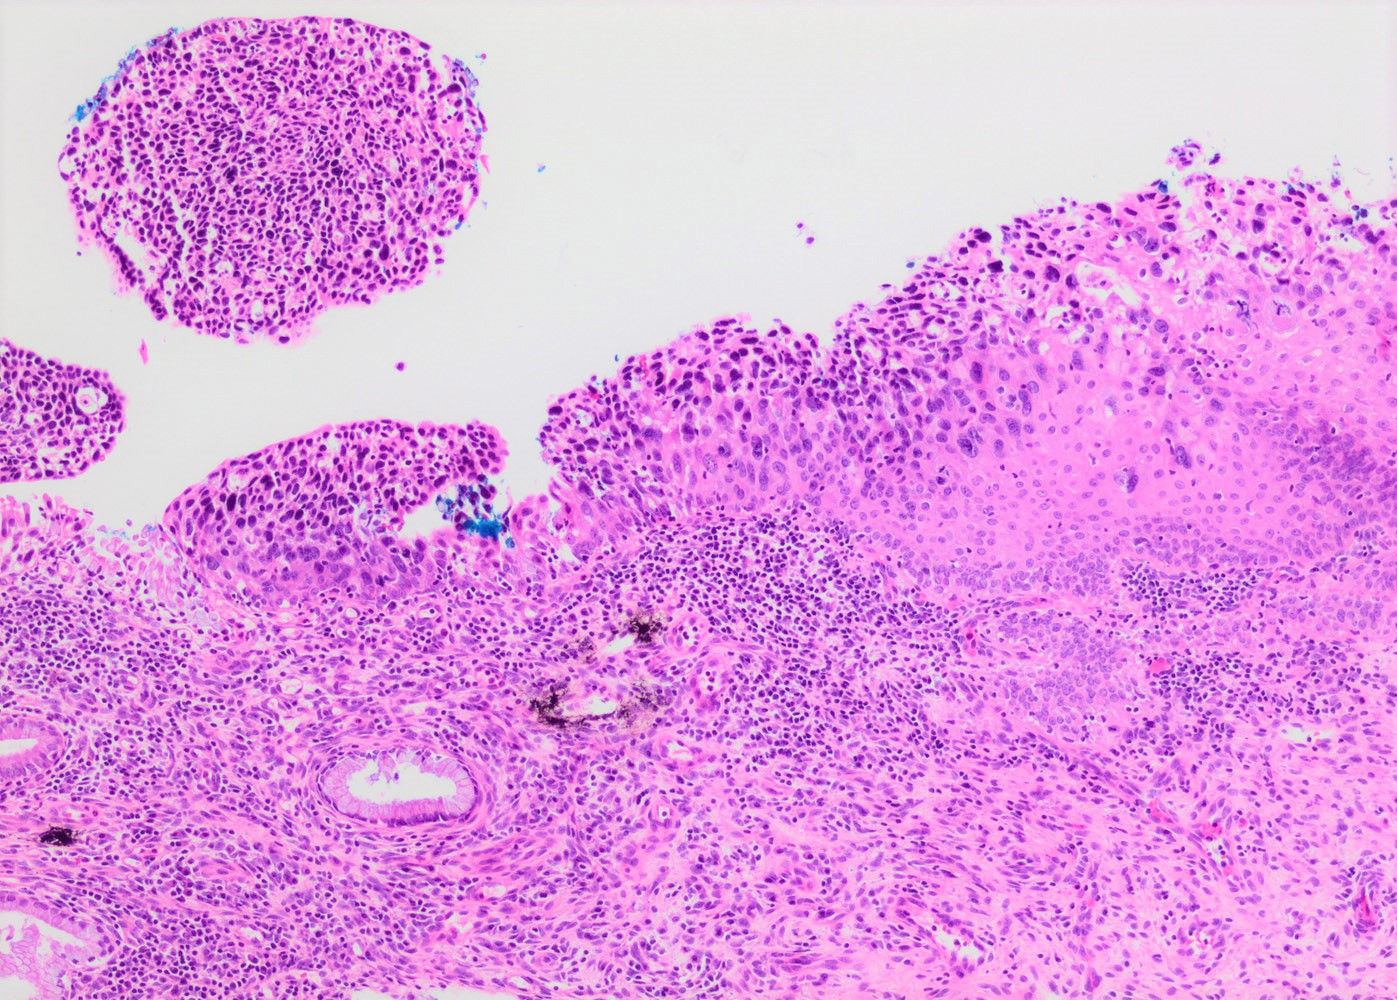

- Conventional / classic pattern: full thickness nuclear abnormalities (hyperchromasia, coarse chromatin, irregular nuclear contours and inconspicuous nucleoli), high N/C ratio in at least lower two - thirds of epithelium

- CIN II: cytoplasmic maturation in the upper third of mucosa

- CIN III: full thickness basal / parabasal type, no maturation difference across layers

- Increased mitotic activity with atypical mitoses

- Other patterns:

- Thin HSIL: < 10 cells thick; can mimic atrophy; usually focal and coexists with conventional HSIL (Histopathology 2019;75:405, Int J Gynecol Pathol 2017;36:71)

- Keratinizing HSIL: superficial keratinization without koilocytosis

- Papillary HSIL: lining endocervical papillae

- Pleomorphic HSIL: focal bizarre nuclear changes / multinucleation (Pathology 2017;49:465)

- May present as small metaplastic type cells mimicking immature metaplastic epithelium (Int J Gynecol Pathol 2007;26:180, Am J Surg Pathol 2014;38:470)

Microscopic (histologic) images

Contributed by Khaled J. Alkhateeb, M.B.B.S.